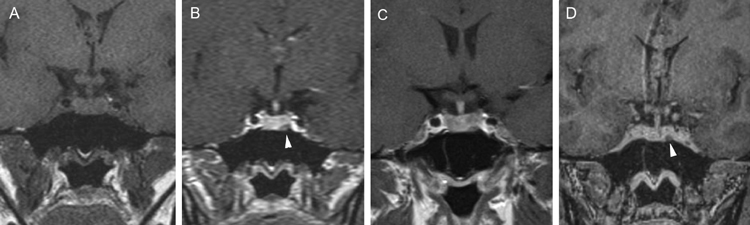

Figura 10A y B. Microadenoma pituitario (prolactinoma), secuencias T1W antes y después de contraste, cortes coronales. Sin Gadolinio el tumor tiene señal similar a la glándula pituitaria. La secuencia T1W post Gadolinio, muestra la glándula contrastada y a izquierda un tumor no contrastado, (hipointenso) de 7 mm (punta de flecha). Características de la imagen del adenoma pituitario